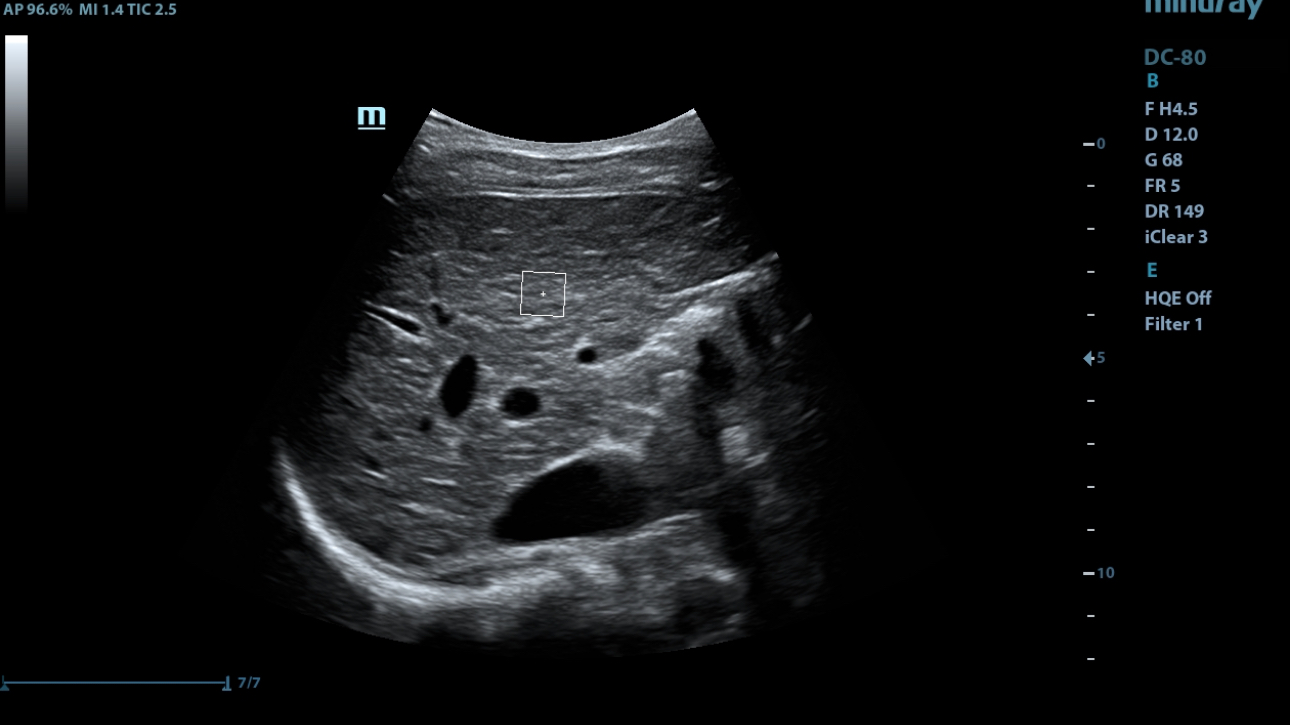

Overview

The best patient care is your ultimate goal. To achieve this requires confident diagnosis even with daily increases in patient throughput. Built on the foundation of MindrayŌĆÖs continuous customer insights into clinical needs and the inheritance from premium technology, the DC-80 with X-Insight is designed to help you manage your daily output with high efficiency, no matter what type patients and clinical challenges you will face.

eXpress Clarity

More clarity at hand

To achieve excellent images with minimal effort is always the highest clinical priority and Mindray's endless pursuit. With continuous innovation of imaging and transducer technologies, X-Insight delivers express clarity as soon as the transducer touches the body.